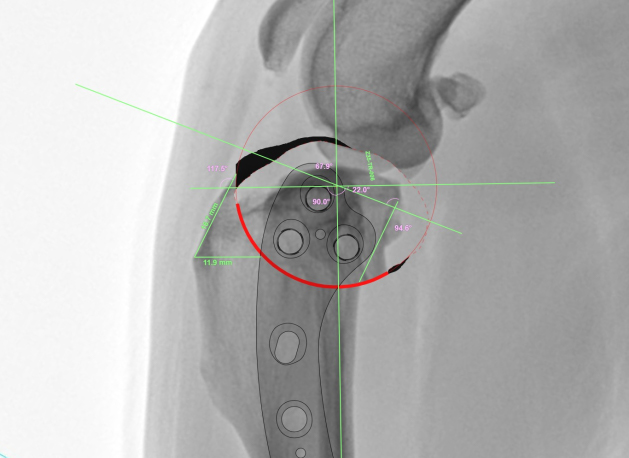

• 수술 전 각도 조정 이미지

04

수술 전 각도 조정

수술 전, 정확한 각도 조정 수술 계획을 수립합니다.